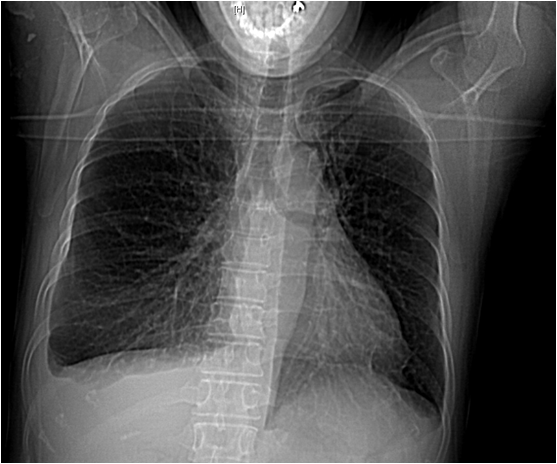

胸片检查

左心增大,右肺中下叶肺组织膨胀不全,右侧胸腔中等量积液